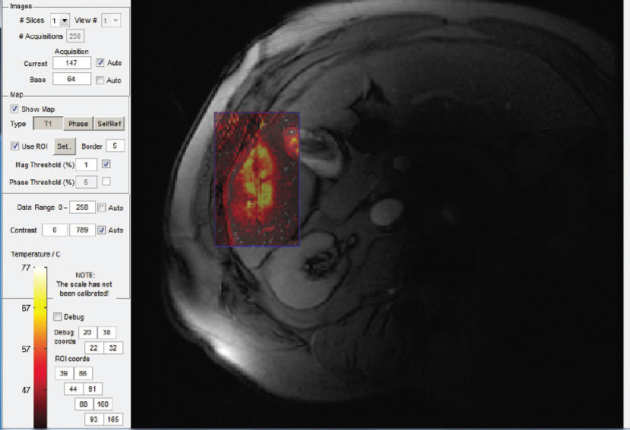

Treatment of otherwise inoperable liver tumours using Laser Ablation (LITT)

Aims

- Improved accuracy using MRI-assisted needle targeting, remote control

- Reduced setup time, overall procedure time

- MR thermometry using interstitial microcoils

- Early patient trial conducted successfully, further trials planned